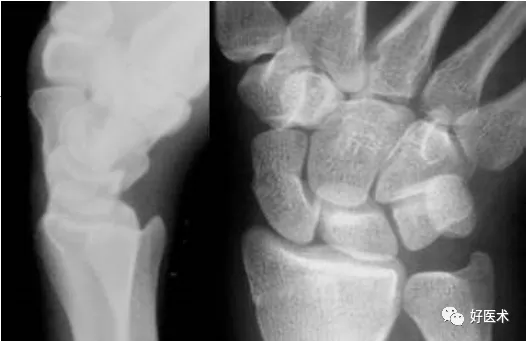

月骨脫位

正位片示舟月關節間隙消失,腕骨弧線不連續;側位片示橈骨遠端的關節面不與月骨平行,月骨倒立,就像立著的一個香蕉或一片橘子,並且向前突出移位。其他腕骨位置正常。

月骨周圍脫位

正位片示M形腕掌線和腕骨弧線不連續,腕骨角140°(>130°);側位片示月骨和橈骨相對位置正常,月骨遠端的凹形關節面空虛,其他腕骨一起向後移位,形似懸掛在月骨後上方的花托。月周脫位常伴有舟骨骨折,本例亦顯示舟骨橫行骨折。